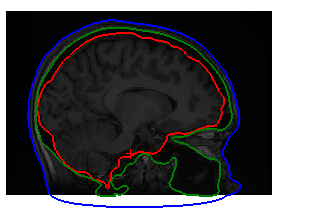

For other subject instead the surfaces are simply wrong (see attached 2), even though make_bem_model hadn't give me any error

This looks reasonable to me but I would like to listen your opinion on that. I don't understand why the surfaces are not registered with the main T1w though.

I have worked in putting down a script that use different tools and in the end the surfaces right now are nicely coregistered with the T1w (see attached). Even though the outer skin is going a little bit outside but it should not be a big deal.